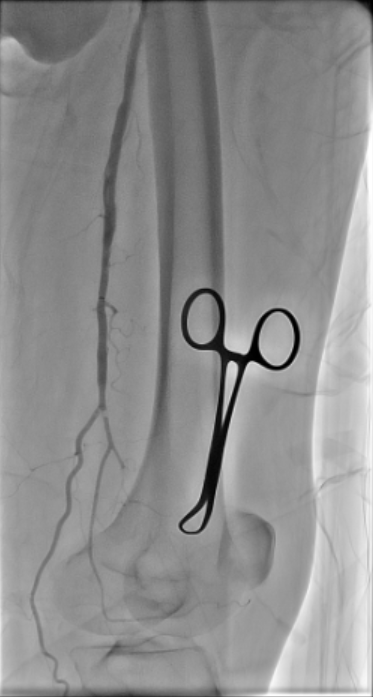

Diagnostic arteriography showed total occlusion of the distal SFA with poor distal runoff. Reconstitution was identified only at the distal ATA as the single suitable target vessel.

Antegrade puncture was performed, and a microcatheter with a Command 14 guidewire (Abbott Vascular, Santa Clara, CA, USA) was advanced toward the distal SFA but failed to cross because the proximal cap was misidentified due to its blunt and ambiguous appearance. The wire entered aside branch that ran parallel to the true SFA–popliteal course. Given the long chronic total occlusion (CTO) segment and uncertain vessel path, a retrograde approach was pursued to overcome this anatomical ambiguity. Distal ATA access was gained and a CXI Support Catheter (Cook Medical, Bloomington, IN, USA) with a V-18 Guidewire (Boston Scientific, Marlborough, MA, USA) was advanced retrogradely into the popliteal artery but failed to meet the antegrade wire. Another retrograde access from popliteal artery followed a consistent tract. Further attempt from the ATA successfully approached the proximal cap. A 4.0 ¡¿80 mm balloon was advanced retrogradely and inflated at 10 atm. From the antegrade route, the BeBack Crossing Catheter (Bentley InnoMed, Hechingen, Germany) was aimed toward the inflated balloon and successfully punctured the proximal cap, entering the balloon and confirming re-entry. Lesion preparation was completed antegradely, followed by drug-eluting stent deployment in the SFA, drug-coated balloon angioplasty of the popliteal–proximal ATA segment, and plain old balloon angioplasty of the distal ATA to DPA. Final angiography demonstrated excellent in-line flow to the plantar arch.